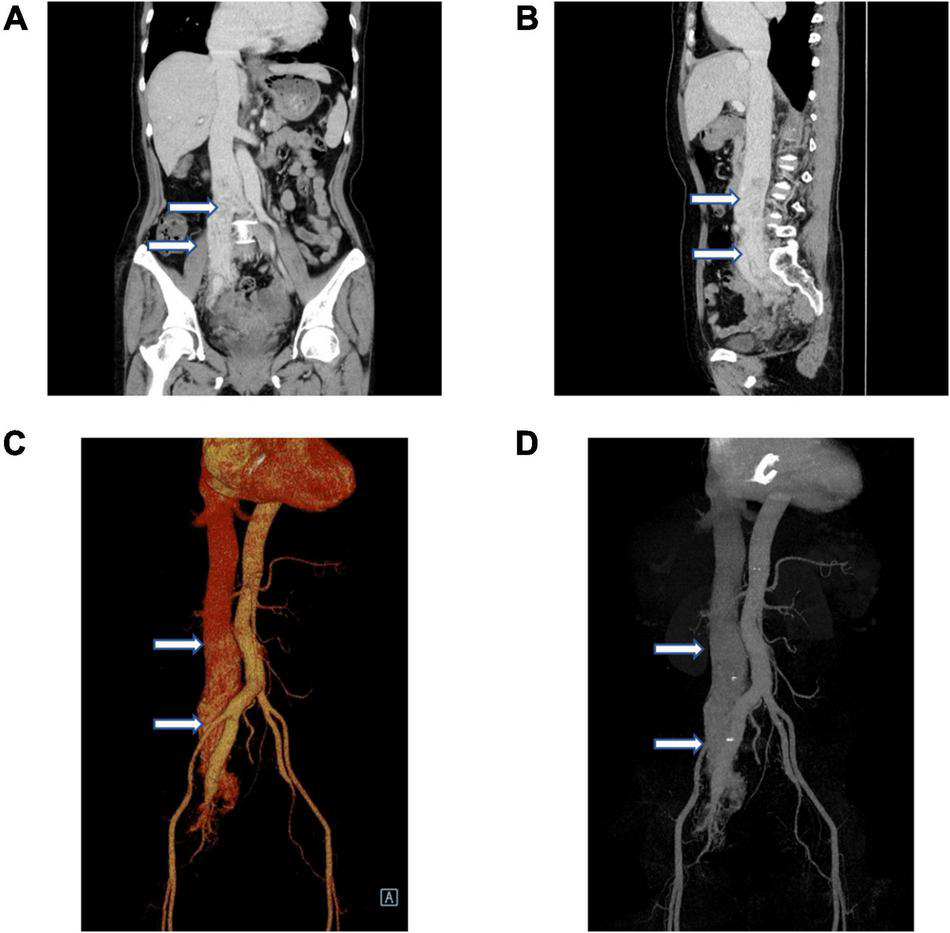

Given the intravenous leiomyomatosis possibilities, gynecological ultrasound was performed and found multiple uterine fibroids and ovarian tumors. Also, lumenal fluid and masses on the uterine fundus posterior wall, extending toward the bilateral internal iliac veins and the inferior vena cava, were found (Figures 2A,B). In addition, computer angiography (CTA) showed that the intravenous leiomyoma involved the right common iliac vein and the inferior vena cava (lower portion), extending toward the renal vein. There was no prominent involvement in the heart and the upper inferior vena cava segments (Figures 3A–D).

FIGURE 3

Vascular computer angiography (CTA) and 3D reconstruction show (A–D) the mass in the posterior wall of the uterine fundus extends to the pelvic veins, bilateral internal iliac veins, and inferior vena cava. The tumor did not invade the superior segment of the inferior vena cava and the heart (white arrows).